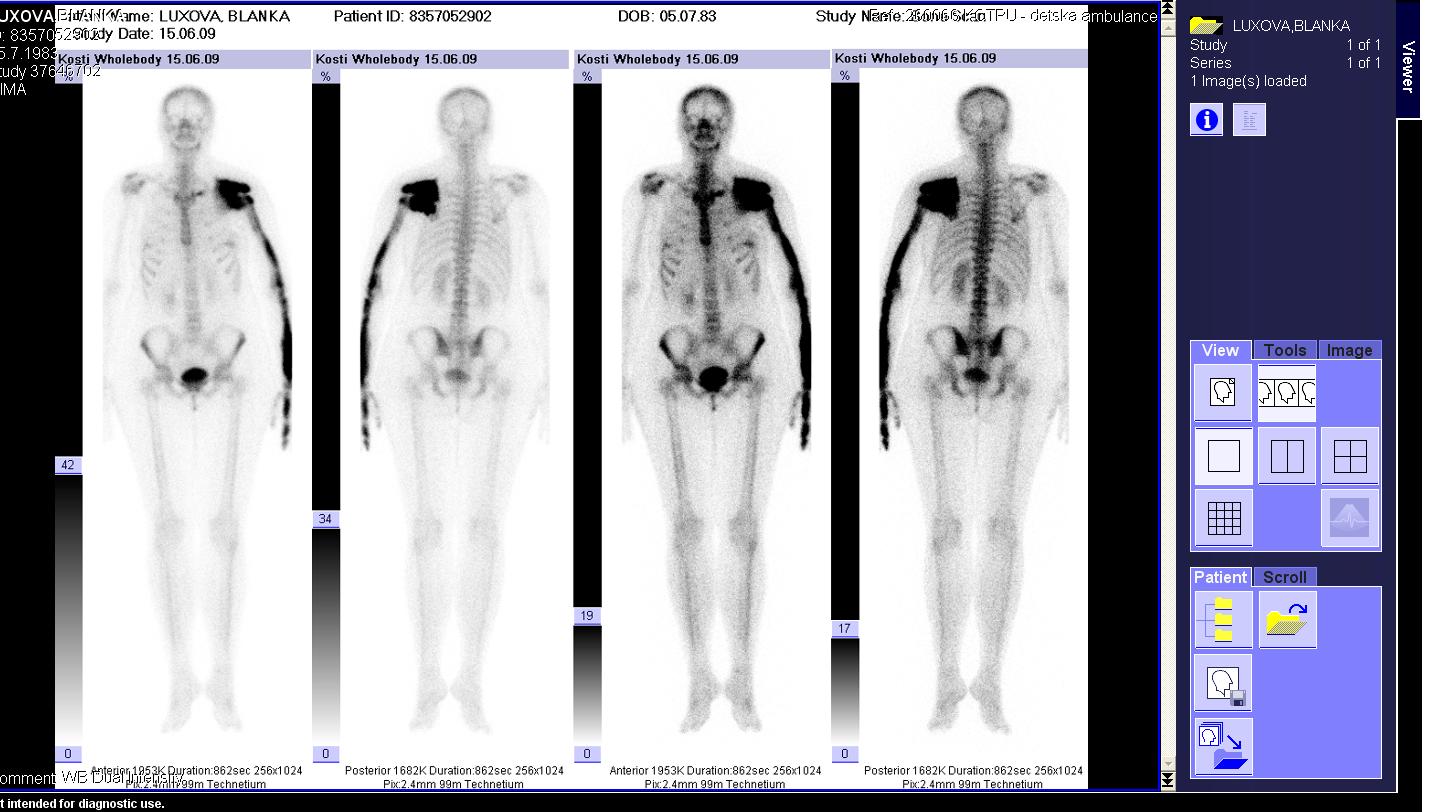

Area(s) affected:  Left arm and hand

I am sending you some photos from RTG and CT and scinti scam from last month.